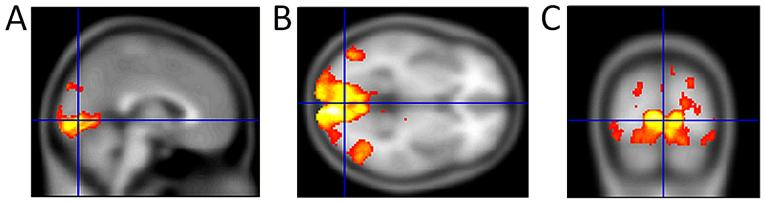

Hypertensive glaucoma is defined as a group of diseases with progressive loss of the neuroretinal margin of the optic disc that causes characteristic degenerative optic neuropathy. The present study provided an updated summary of the physiology and pathology of neurotransmission in the visual path, with the focus on glaucoma. The results of positron emission tomography, functional magnetic resonance imaging and mainly electrophysiological methods demonstrated pathogenesis of nerve cell damage in the visual pathway. Based on these conclusions, neuroprotection in glaucoma was proposed. This consists mainly of the reduction of the intraocular pressure. It is followed by a decrease of glutamate in the synaptic cleft and blockade of its binding to the NMDA receptors. The supply of energy substrates to altered nerve cells is also indispensable. Therapy should be systemic due to impairment of the complete visual path.

高血压性青光眼被定义为一组疾病,其特征是视盘神经视网膜边缘逐渐丧失,导致典型的退行性视神经病变。本研究提供了视觉通路神经传递生理和病理的最新综述,重点是青光眼。正电子发射断层扫描、功能磁共振成像以及主要的电生理方法的结果证实了视觉通路中神经细胞损伤的发病机制。基于这些结论,提出了青光眼的神经保护措施。这主要包括降低眼压。其次是减少突触间隙中的谷氨酸,并阻断其与NMDA受体的结合。向发生改变的神经细胞供应能量底物也是必不可少的。由于整个视觉通路受损,治疗应是全身性的。